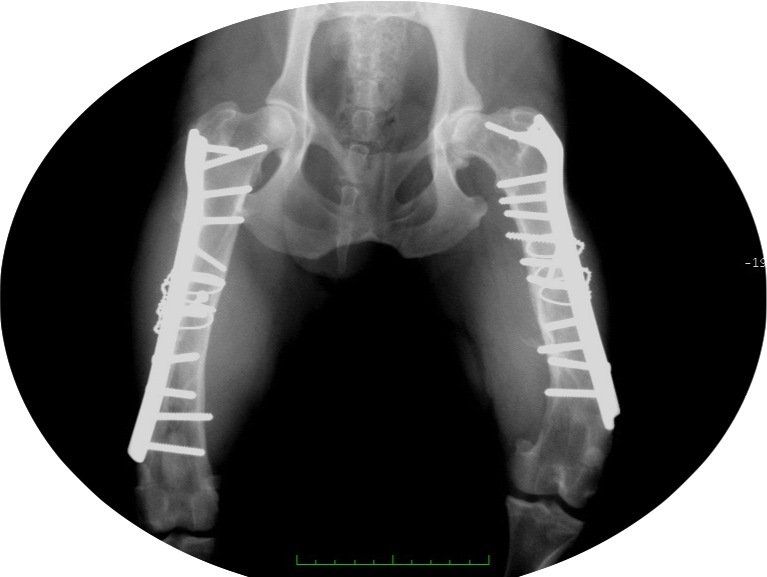

- Les chirurgies réparatrices lors de fractures des membres avec utilisation de broches, plaques et vis.